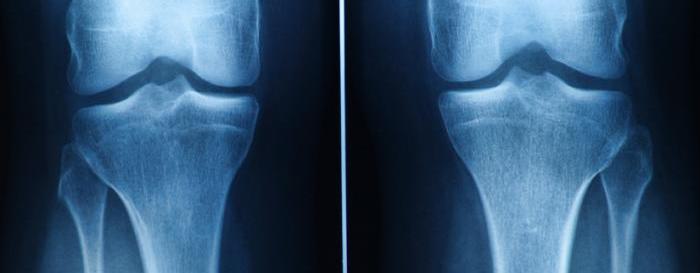

Treatment Options for Cartilage Damage

Current treatments focus on symptom relief or joint replacement for severe cases.